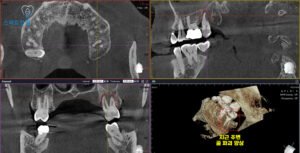

정밀한 확인을 위해

엑스레이 사진을 촬영해 보기로 했어요.

25.09

파노라마와 CT 상에서 치아 뿌리 주변으로

심한 골 파괴 양상이 보였으며,

이는 치아를 지탱하는 뼈가 크게

손상된 상태임을 시사했습니다.

이러한 골 파괴는 치아의 안정성을 위협하는데요.